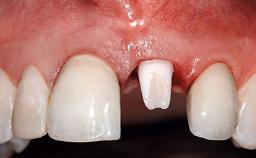

Replacement of a Compromised Upper Right Central Incisor: Hard- and Soft-tissue Augmentation, Late Placement of an RC Bone Level Implant

A 36-year-old male patient with a compromised maxillary central incisor was referred by his general dentist for consultation. The patient’s chief complaints were the gradual debonding of a temporary crown on the right central incisor and unsatisfactory esthetics due to an increasing diastema between the right central and lateral incisors. The patient reported a traumatic event some years previously, when a crown had been placed after root-canal treatment. The referring dentist wanted to provide a new crown restoration, but was concerned about the condition of the residual root. Anamnesis was negative for any other dental or periodontal pathology in the remaining dentition. The patient reported taking no medications: He was a smoker (10 to 15 cigs/day) and had realistic esthetic expectations.

Prosthesis Type FDP